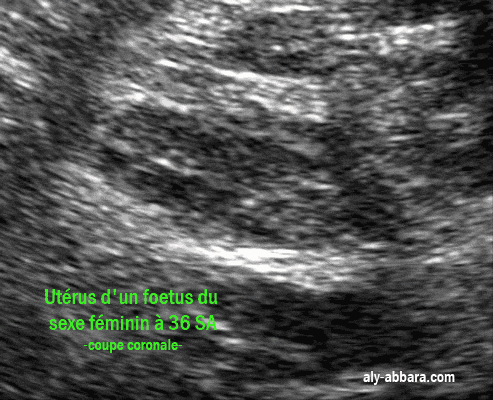

Une coupe échographique coronale de l'utérus d'un foetus du sexe féminin à 36 semaines d'aménorrhée

Sur cette image, on peut constater que le rapport (longueur corps utérin/longueur du col ) est presque égale à un

Puis on remarque l'épaississement de l'endomètre sous l'effet des hormones sexuelles maternelles qui traversent

la barrière materno-placentaire